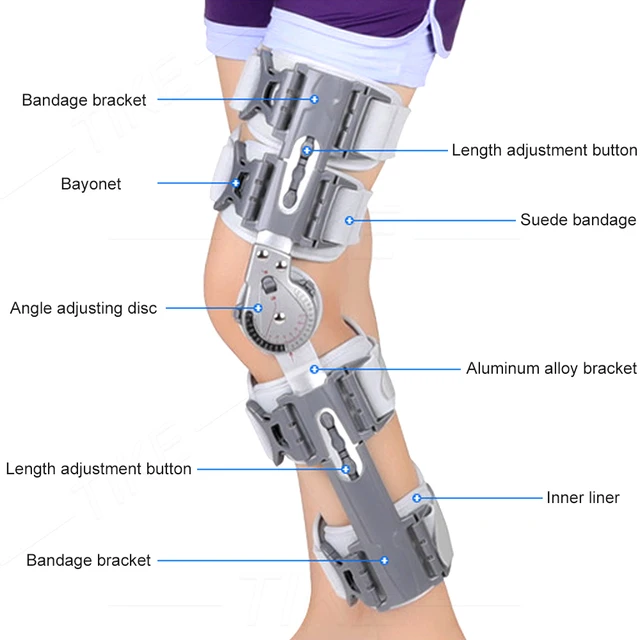

Tike Rom Csuklós Térdtartó Immobilizáló Ortózis Stabilizátor Acl Mcl Pcl Sérüléshez, Az Ortopédiai Rehabilitációs Poszt Helyreállítási Támogatása

Darabszám: Egy egység

Alkalmazás: Láb

Hatás: Bone Care

Anyaga: kompozit anyag

Modellszám: csuklós térdmerevítő

Elem típusa: merevítők és támasztékok

Szín: ezüst

Alkalmazható személyek: Felnőtt férfiak, nők

térdtámasz: műtét utáni térdmerevítő

lábmerevítő: acl sérülés térdmerevítő

acl merevítő: acl műtét utáni merevítő

térdmerevítő: post op térdmerevítő

térdstabilizátor: teljes hosszúságú csuklós térdmerevítő

térdmerevítő: térdmerevítő mcl sérülés

térdeszköz: molett térdmerevítő

csuklós merevítő: post op acl térdmerevítő

térdmerevítő: reteszelő csuklós térdmerevítő

acl csuklós merevítő: nagy csuklós térdmerevítő

csuklós térdmerevítő: térdmerevítő zárral

acl merevítő térd: térdmerevítő acl műtét

térdmerevítő műtét: csuklós acl térdmerevítő

stabilizáló térdmerevítő: mcl térdmerevítő csuklós

lábstabilizáló merevítő: csuklós térdtámasztó merevítő

zárt térdmerevítő: csuklós jobb oldali térdmerevítő

stabilizátor térdmerevítő: mcl térdmerevítő csuklós stabilizátor

mcl brace térd: orvosi térdmerevítő zsanérral

acl javító merevítő: meniszkusz térdmerevítő műtét után

pcl térdmerevítő: csuklós térdmerevítő stabilizátor

sípcsont térdmerevítő: állítható zárható térdmerevítő

térdtámasz: állítható, rögzítő térdmerevítő

teljes lábmerevítő: a legjobb térdmerevítő műtét után

hibged térdmerevítő: post op csuklós térdmerevítő

csuklós lábmerevítő: térdmerevítő oldalsó stabilizátorokkal